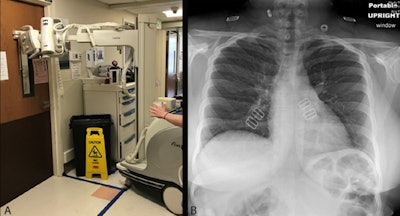

Chest radiography through glass. (A) A technologist positions the portable radiography unit outside the patient room with the x-ray tube facing the wire-reinforced isolation room window. (B) Anteroposterior chest radiograph obtained through glass is of diagnostic quality. Images courtesy of the RSNA.Importantly, since the portable radiography machine was never in the patient's room, it does not require cleaning, the authors noted.

The TG-CXR method involves having only one technologist don PPE and enter the isolation room to position the patient and cassette/detector. A second technologist stays with the portable x-ray machine outside of the isolation room. Once the patient is in a satisfactory position, the first technologist provides breathing instructions to the patient and then signals the second technologist to trigger the exposure. While the first technologist waits in the isolation room, the second confirms that the acquired image is of satisfactory quality.